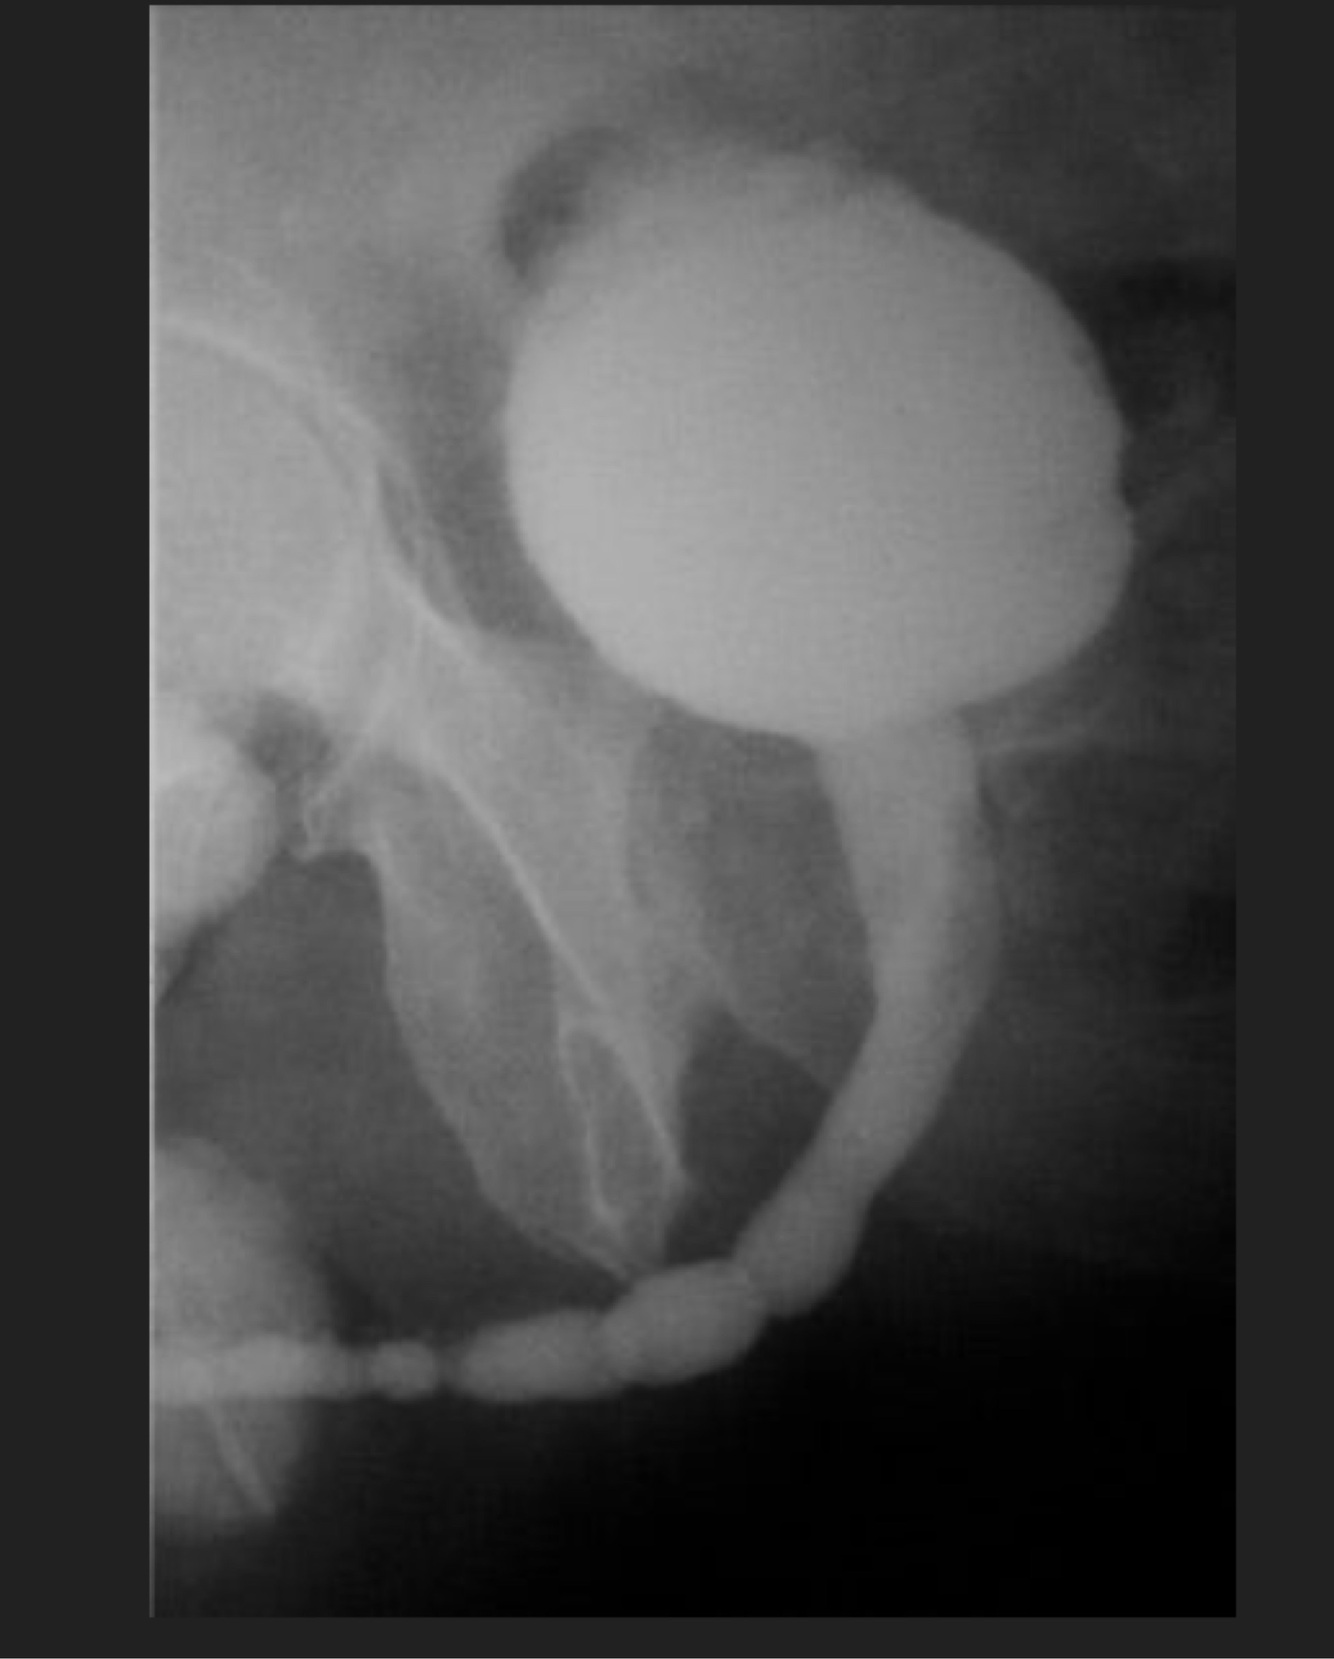

3

Q

Cistograma con datos de:

A

Divertículos vesicales